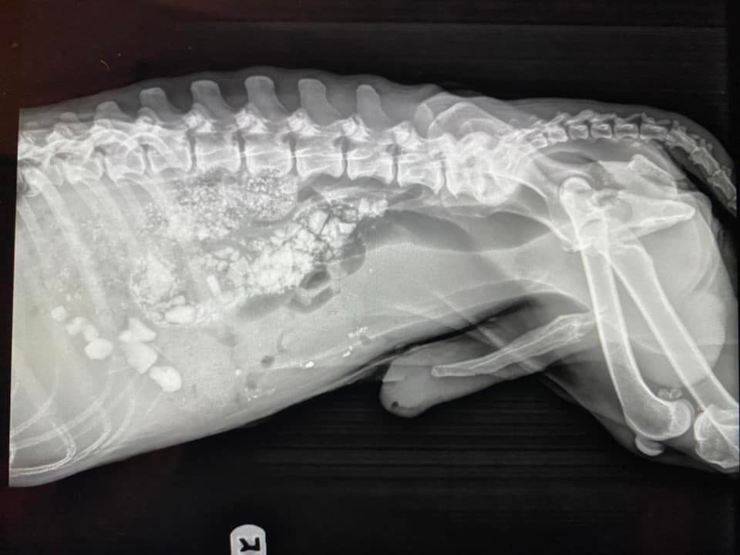

Nonostante fosse letteralmente pelle e ossa, il cane aveva la pancia gonfia e soffriva di diarrea. I volontari l’hanno condotto d’urgenza da un veterinario per controllare le sue condizioni. Le radiografie hanno svelato una triste e amara verità.

Il povero cane affamato aveva mangiato sassi per quietare i morsi della fame e cercare di sopravvivere nella discarica.

Il Fido è stato trasferito allo Spencer Springs Animal Hospital. Le radiografie hanno mostrato numerosi sassolini all’interno dell’intestino del cane. Lo staff dell’associazione e i veterinari si augurano che i corpi estranei ingeriti dall’animale non causino un’occlusione intestinale poiché, in tal caso, sarebbe necessario ricorrere ad un intervento chirurgico.